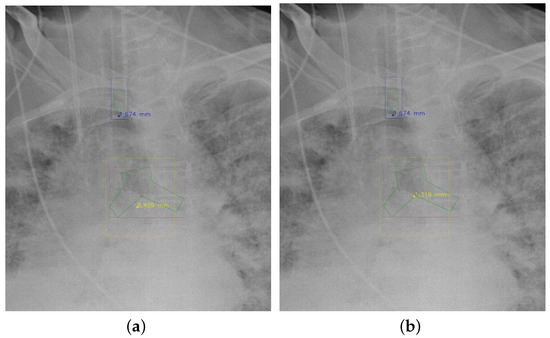

4.5.7. The Post-Process Algorithm

Figure 7 and Figure 8 demonstrate the effect of post-processing. The red bboxes and points in these figures are the GT ETT/bifurcation bboxes and the position of GT ETT tip/Carina, respectively. The green polygon is the GT mask of the ETT and the bifurcation. The blue bbox and point are the predicted ETT bbox and ETT tip, respectively. The yellow bbox and point are the predicted bifurcation and Carina, respectively. Specifically, without the post-process, the model might leave more than one predicted ETT tip/Carina, such as where the red arrow points in Figure 7a. However, with the post-process, the extra points would be removed as shown in Figure 7b. Besides, with the refinement process in the post-process, the feature point of ETT tip/Carina could be further refined as shown in Figure 8. Concretely, the object error of Carina was corrected from 8.469 mm to 1.319 mm.

Figure 8. Refining the feature point of ETT tip/Cairna by the bbox of ETT/Bifurcation. (a) Without post-process. (b) With post-process.

Diagnostics 12 01913 g008